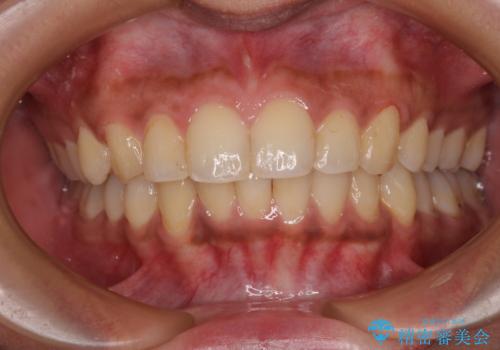

- ぼろぼろになった奥歯を治療したいとのことで来院された患者様です。

重度の歯周病と歯列不正が認められたため、歯周病治療やインプラントによる咬合回復を行った後に矯正治療を実施し、最終的にオールセラミッククラウンに補綴することとしました。

インプラント治療や歯槽骨再生治療、矯正治療など、盛りだくさんの治療計画であったため、治療期間は最低でも4年という予想でした。

歯列不正などによるプラークコントロールの不良が治療を困難なものとしましたが、矯正治療後は歯肉の状態も落ち着き、安定した状態でオールセラミッククラウンの補綴を行うことができました。

治療期間が大変長かったため、治療を終えたときには患者様の喜びもひとしおといった感じでした。